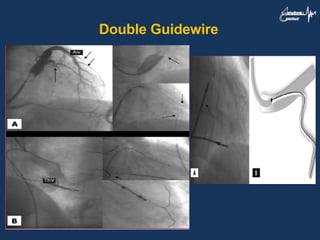

Double Guidewire

Sharply Angulated orTortuous Target Vein 1. Use an appropriately shaped inner sheath that can selectively hook the target vein 2. Other techniques include pushing the wire as much inside the vein as possible to gain extra support, or to pull the wire while advancing the lead 3. Using second stiffer wire to reduce the tortuosity and provide extra support